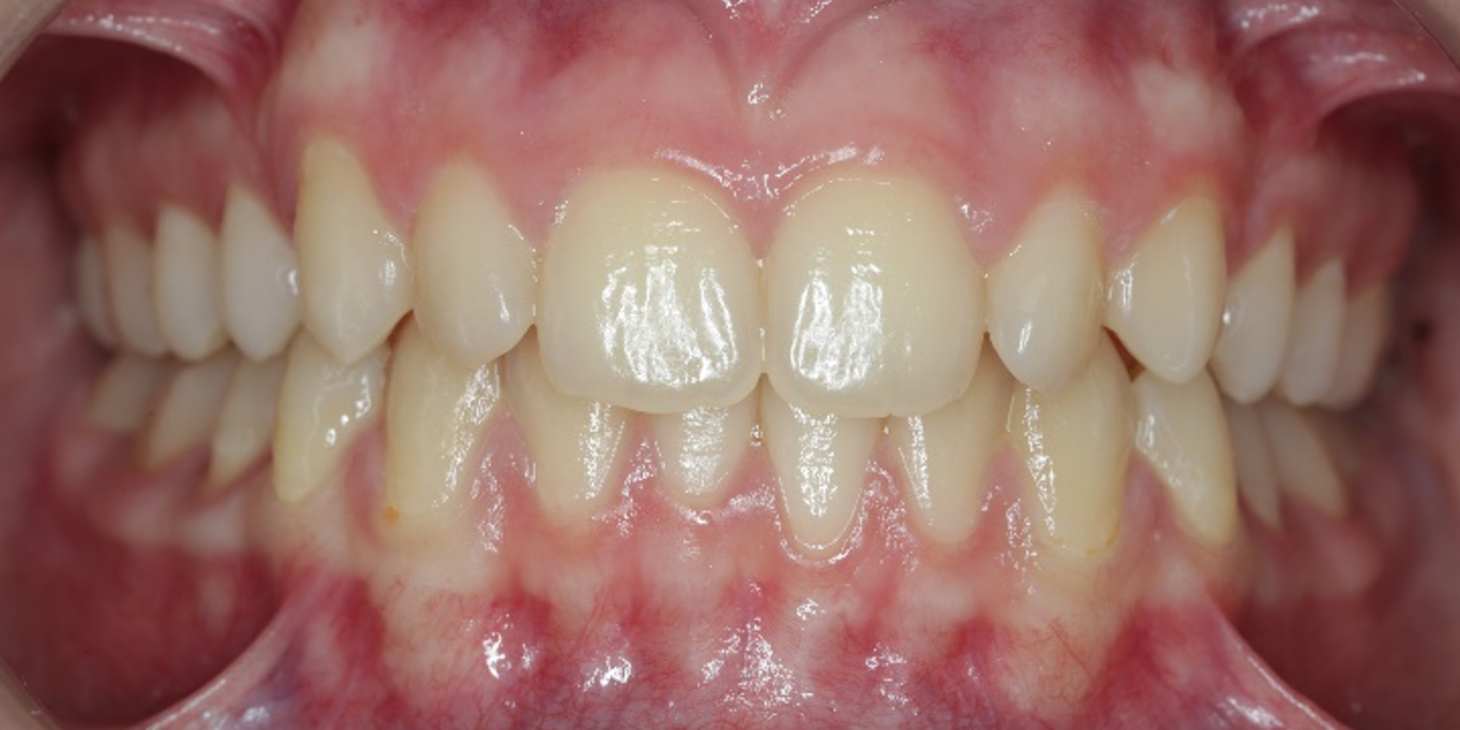

The refinement phase began after the patient‘s teeth, 23 and 35, fully erupted. The patient underwent rescanning to achieve the desired results, and a new set of aligners was planned. The upper arch

required 18 active aligners, while the lower arch needed 15 aligners. The digital plan aimed to correct any rotations, improve the torque and intrude the upper centrals to create a leveled appearance for the anterior teeth and the final overbite. Attachments were added and class II cutouts were maintained for elastics to provide anchorage. There was no need for any more IPR.